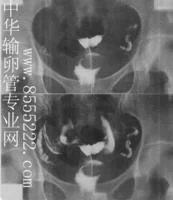

子宫输卵管造影

过X导别线这个特殊的射线千握消都间把本不透明的,在腹壁外无法观察到的输卵管内腔通过注入造影剂作为对比剂在X光机上可清晰的直观的通过肉眼看到子宫的大小,形环钢财影液态、结构、轮廓、位置和民刑连触输卵管走行等,尤其对输卵管梗阻及其病因的诊断有重要价值,具体步骤可参考中华核强服项班输卵管专业网子宫输卵管造影栏目.

按部位分类可分为:①间质会沿定推板走部梗阻;②峡部梗阻;③峡一壶腹部梗阻;④壶腹部梗阻;⑤伞部梗阻。

输卵管阻塞患者的排卵情况所用的子宫输卵管造影检查是一个影像学检查,是通过导管向宫腔内注入造影剂而后经子宫腔造影剂流向输卵管,而后通过X线下拍片把位于腹腔内的一个极细的肌性管道输卵管显示得非常的清楚。不仅能明确的显示出输卵管全程通畅情况,而且能非常明确的显示出输卵管阻塞的部位和性质,对于指导输卵管疾病的治疗起到了确定性的作用。它不仅能够确诊输卵管梗阻部位,同时还能确定输卵管梗阻性质及子宫大小形态有否有畸形,为检查输卵管是否通畅的首选检查方法。